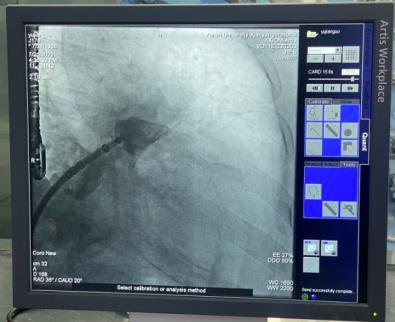

穿刺房間隔后置入6F豬尾導(dǎo)管,于CAU20°,RAO35°進(jìn)行左心耳造影,可見(jiàn)左心耳為大角度反雞翅形,測(cè)量左心耳開(kāi)口26mm,深度25mm。各位在線的專(zhuān)家有張玉順教授、宋治遠(yuǎn)教授、胡浩教授等,進(jìn)行了熱烈討論后,一致認(rèn)為該例手術(shù)難度較大,封堵傘不易釋放。

經(jīng)過(guò)仔細(xì)讀圖,發(fā)現(xiàn)左心耳下葉可作為封堵主軸向,該方向避免了大角度反折,但深度略淺,手術(shù)難度仍是不小。最終選取30mmWATCHMAN封堵器。